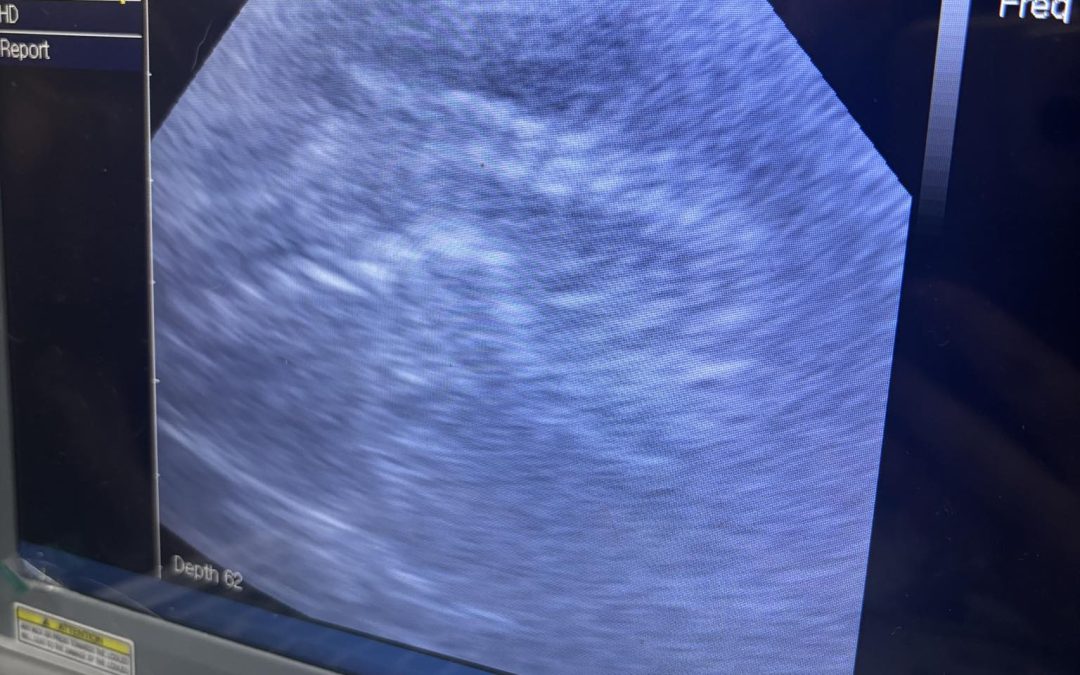

Service: Dog Ultrasound Scan Chorley Location: Chorley,  Lancashire How We Helped: Ultrasound check-up scan carried out today here at Preston’s K9 fertility services on a mini dachshund with about a week left of pregnancy Puppies are all looking great. Located...